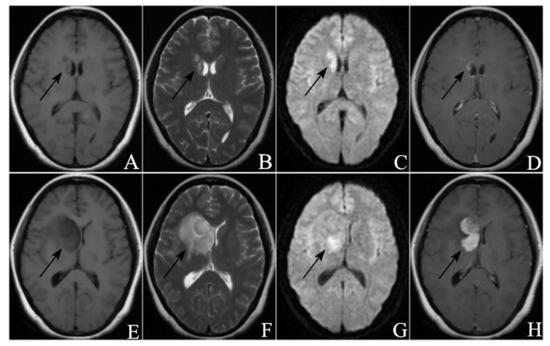

3.2. Radiological Manifestations